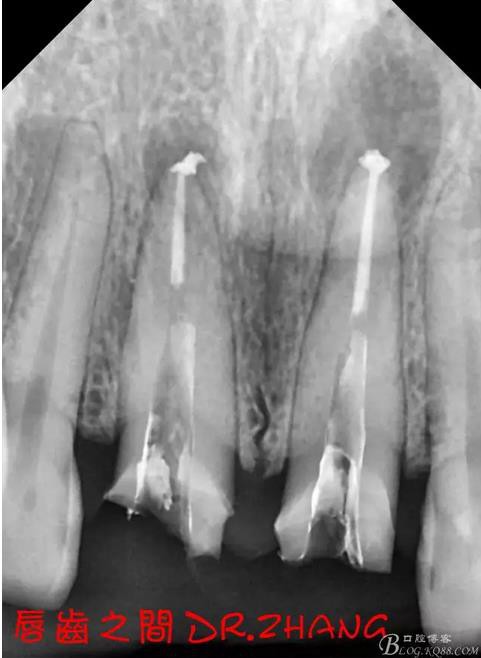

檢查:11 21金屬烤瓷冠 21根尖部牙齦紅腫 牙痛 叩(+++)冷刺激無反應(yīng) 11無不適癥狀 全口牙周情況良好

X片示11 21根管內(nèi)有高密度陰影 根尖低密度陰影

診斷:11 21慢性根尖炎